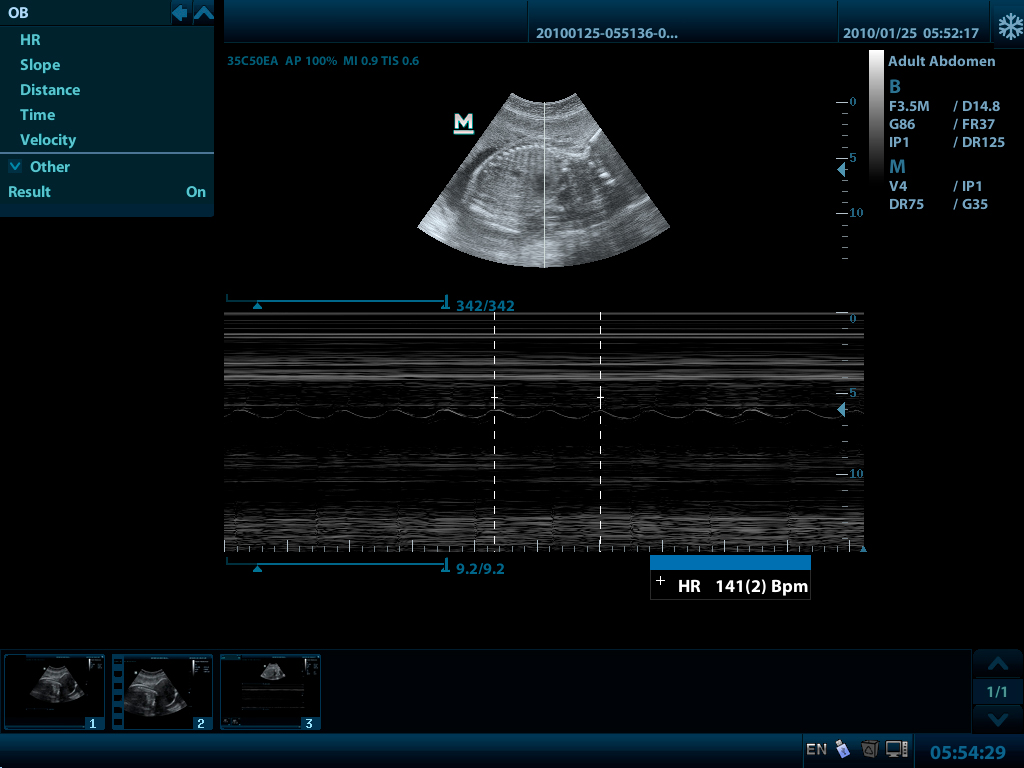

Mindray DP-50 – портативная цифровая ультразвуковая система с ЖК монитором 15 дюймов (1024Х768)

и встроенными аккумуляторными батареями (опция) позволяющими работать в автономном режиме до 2-х часов.

- THI - режим тканевой гармоники

DP-50 – портативный УЗИ сканер разработан на базе новой платформы X-treme engine, используемой в хорошо зарекомендовавших себя цветных сканерах с доплером моделей DC-3, DC-7, DC-6. Эта платформа открывает возможности для расширений до уровня цветных сканеров и совместимости с широким диапазоном периферийного оборудования. X-treme означает интеллект, высокую скорость обработки данных, многоуровневую передачу сигналов, а также возможность оптимизации изображения и модульного расширения.

Конвексный датчик 35C50EA (2.0/3.5/4.5/5.0/Н5.0/Н6.0) R50